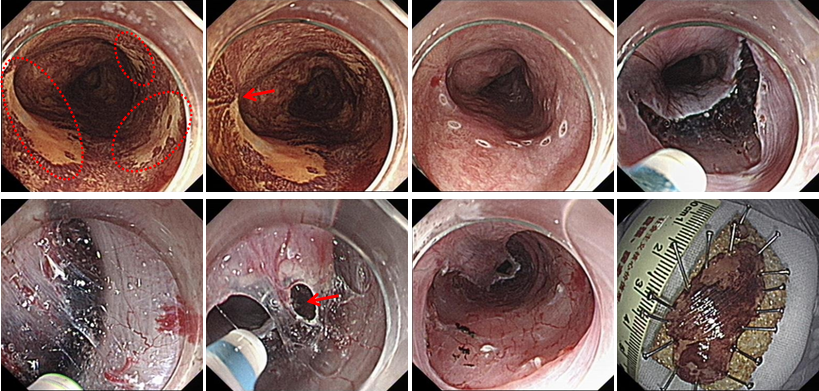

ESTD治疗多灶性复发型食管早癌

ESD治疗超低位大面积直肠早癌

STER治疗食管固有肌层肿瘤